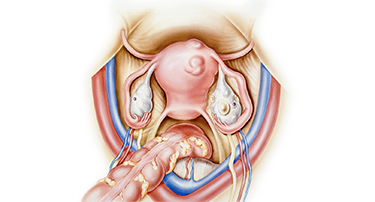

Uterine Prolapse Treatment Without Hysterectomy – Robotic Options

Uterine prolapse happens when the muscles and ligaments in the pelvic area become weak, causing the uterus to sag into the vaginal canal.

Oophorectomy refers to major surgery in which one or both of the ovaries are removed. It is recommended for treating various gynecological conditions, such as ovarian cysts, tumors, or endometriosis.

How To Recognize And Manage Gynaecological Diseases Early

Women frequently encounter many different health problems that particularly influence their reproductive tract. They are referred to as gynaecological diseases and can occur in the uterus, ovaries, fallopian tubes, vagina, or breasts.

Endometriosis: Myths, Symptoms & Treatments

Endometriosis is a widespread but frequently misconceived disorder affecting millions of women globally. Endometriosis happens when endometrium-like tissue develops in places outside the uterus, resulting in pain, inflammation, and occasionally fertility complications.

Fibroids & Ovarian Cysts: Symptoms & Treatment Options

Many women experience changes in their reproductive health at some point in their lives, sometimes without even realizing it. Conditions like uterine fibroids and ovarian cysts are surprisingly common, yet they often remain shrouded in mystery. This blog breaks down these conditions, explaining their symptoms, causes, and treatment.